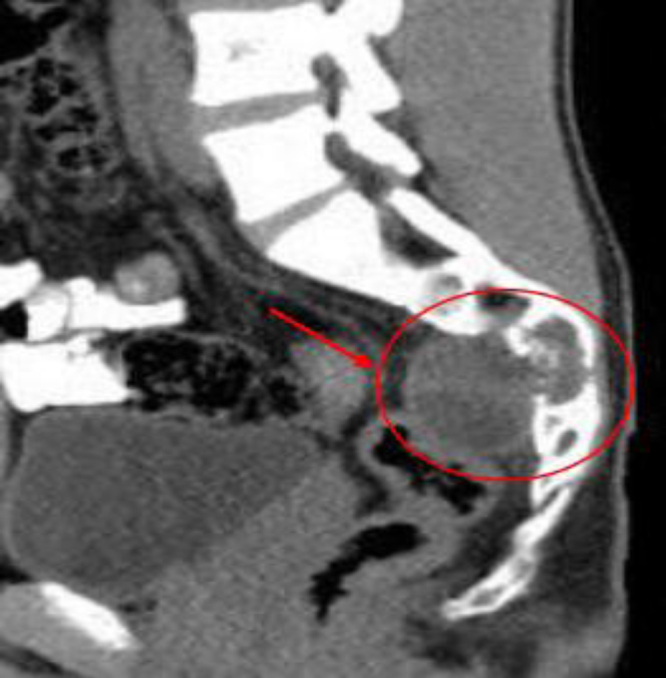

Observations: A 17-year-old male with a history of HC disease presented with low back pain radiating to both lower limbs, claudication, and chronic constipation for 5 years. Imaging revealed a large, multiloculated sacral cyst extending retrorectally and presacrally from S3 to S5, involving the spinal canal, compressing the rectum, and causing sacral erosion. A diagnosis of sacral hydatidosis was made, and the patient was started on albendazole, with surgical excision planned.